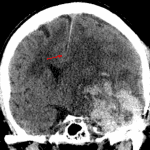

- Large acute parenchymal hematoma centered in the left temporal resection bed measuring 8.5 x 6 x 5.5 cm (volume = 140 mL) with surrounding vasogenic edema

- Associated mass effect with left hemispheric sulcal effacement, left to right midline shift measuring 13 mm at the Foramen of Monro with left subfalcine herniation, near complete effacement of the left lateral ventricle, and left uncal herniation with partial effacement of the suprasellar cistern and mass effect upon the midbrain

- Small amount of hemorrhage extending into the left lateral ventricle

- Mild dilation of the posterior body and atrium of the right lateral ventricle

Large acute parenchymal hematoma centered in the left temporal resection bed measuring 8.5 x 6 x 5.5 cm (volume = 140 mL) with surrounding vasogenic edema. Associated mass effect with left hemispheric sulcal effacement, left to right midline shift measuring 13 mm at the Foramen of Monro with left subfalcine herniation, near complete effacement of the left lateral ventricle, and left uncal herniation with partial effacement of the suprasellar cistern and mass effect upon the midbrain. No cerebellar tonsillar herniation.

Small amount of intraventricular hemorrhage in the left lateral ventricle. Mild dilation of the posterior body and atrium of the right lateral ventricle raises concern for developing noncommunicating hydrocephalus.